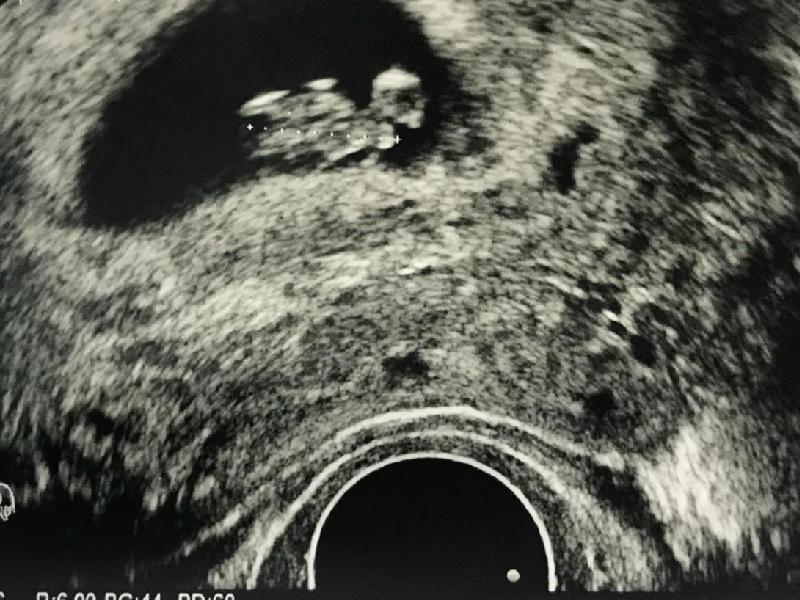

從網傳健檢報告顯示,人員性別一欄為男,而在下方的檢查結果中卻顯示該男子查出了子宮,並有子宮呈前位、形態規則、壁薄內清等報告結果。

男子以為自己得了怪病,事後回到醫院,沒想到工作人員解釋,是數據搞錯了,是前面一名檢測者的數據沒有刪除,直接黏到唐男的報告上,醫院事後除了道歉還表示男子可以再來醫院做一遍健檢。不過唐男表示,他會換一家醫院做健檢。